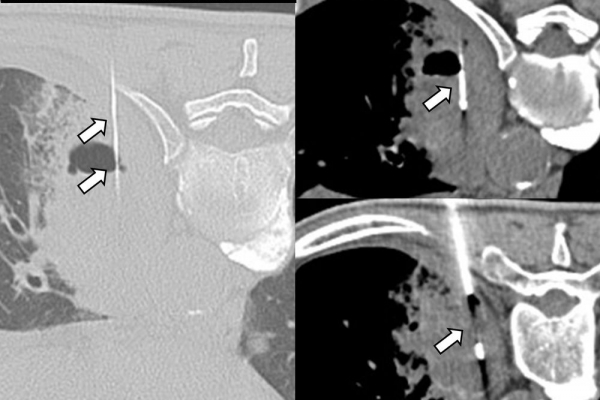

Η διαδερμική βιοψία είναι μία ελάχιστα επεμβατική μέθοδος λήψης υλικού από τον όγκο για κυτταρολογική και ιστολογική εξέταση, από εστιακές αλλοιώσεις του ήπατος, πνεύμονα, νεφρού κλπ. Συστήνεται από τον κλινικό ιατρό ανάλογα με το είδος και το μέγεθος της βλάβης και πραγματοποιείται με ασφάλεια από επεμβατικό ακτινολόγο με την καθοδήγηση αξονικού τομογράφου ή υπερήχων. Στη σύγχρονη ογκολογική θεραπεία όπου γίνεται προσπάθεια καταπολέμησης του καρκίνου σε μοριακό επίπεδο κρίνεται αναγκαία η ακριβής ιστολογική ταυτοποίηση του όγκου ώστε να εφαρμοσθεί εξατομικευμένη θεραπεία για το βέλτιστο αποτέλεσμα. Οι κατευθυνόμενες βιοψίες στοχευουν στο να παρέχουν στον κλινικό ογκολόγο το απαραίτο ιστοπαθολογικό υλικό που θα του επιτρέψει να εφαρμόσει την κατάλληλη θεραπεία για τον ογκολογικό ασθενή.